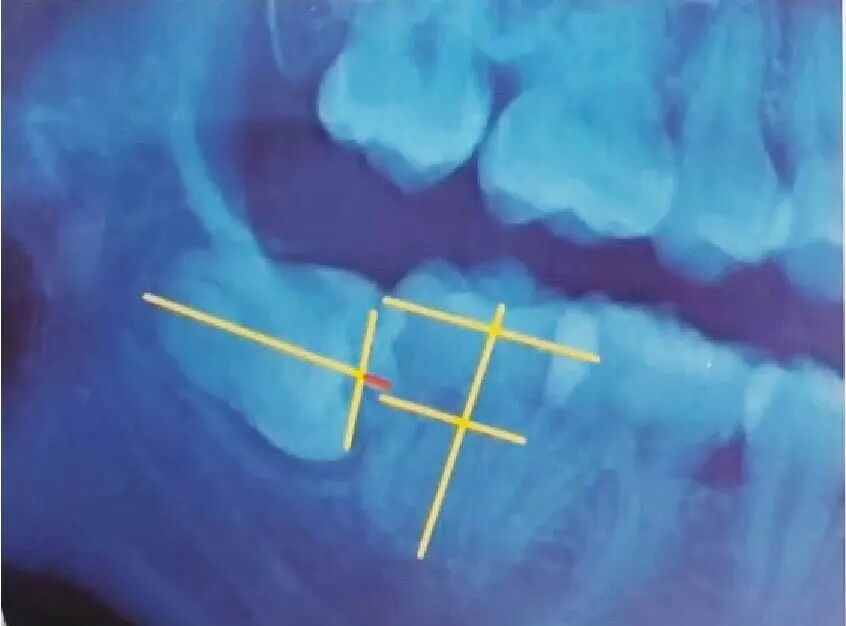

2)

下颌近中倾斜

中位阻生

阻生齿-04.jpg

冠部外形高点线与髓室底之间部位为中位。